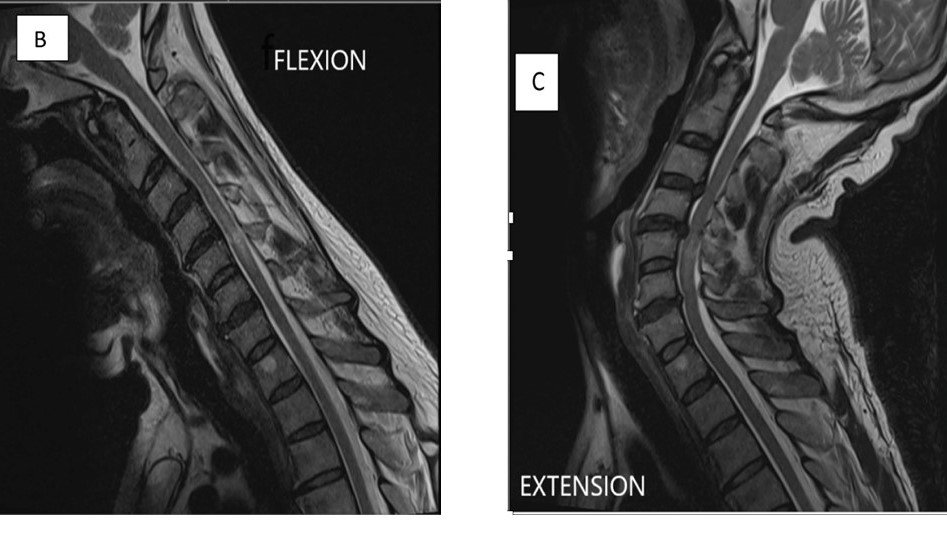

Acute Transverse Myelitis

• No external compression of spinal cord.

• Long-segment intramedullary T2 hyperintensity.

• Cord may appear swollen.

• Central cord involvement common.

• Patchy enhancement may be seen.

• Lesion extends over more than 3 vertebral segments.

• Central gray matter involvement.

• No cord compression.

• Bright T2 signal.

• Suggestive of NMO spectrum disorder.

• Short-segment lesion (<2 vertebral segments).

• Partial cord involvement.

• No cord expansion.

• Minimal or no enhancement.

• Often associated with brain lesions.